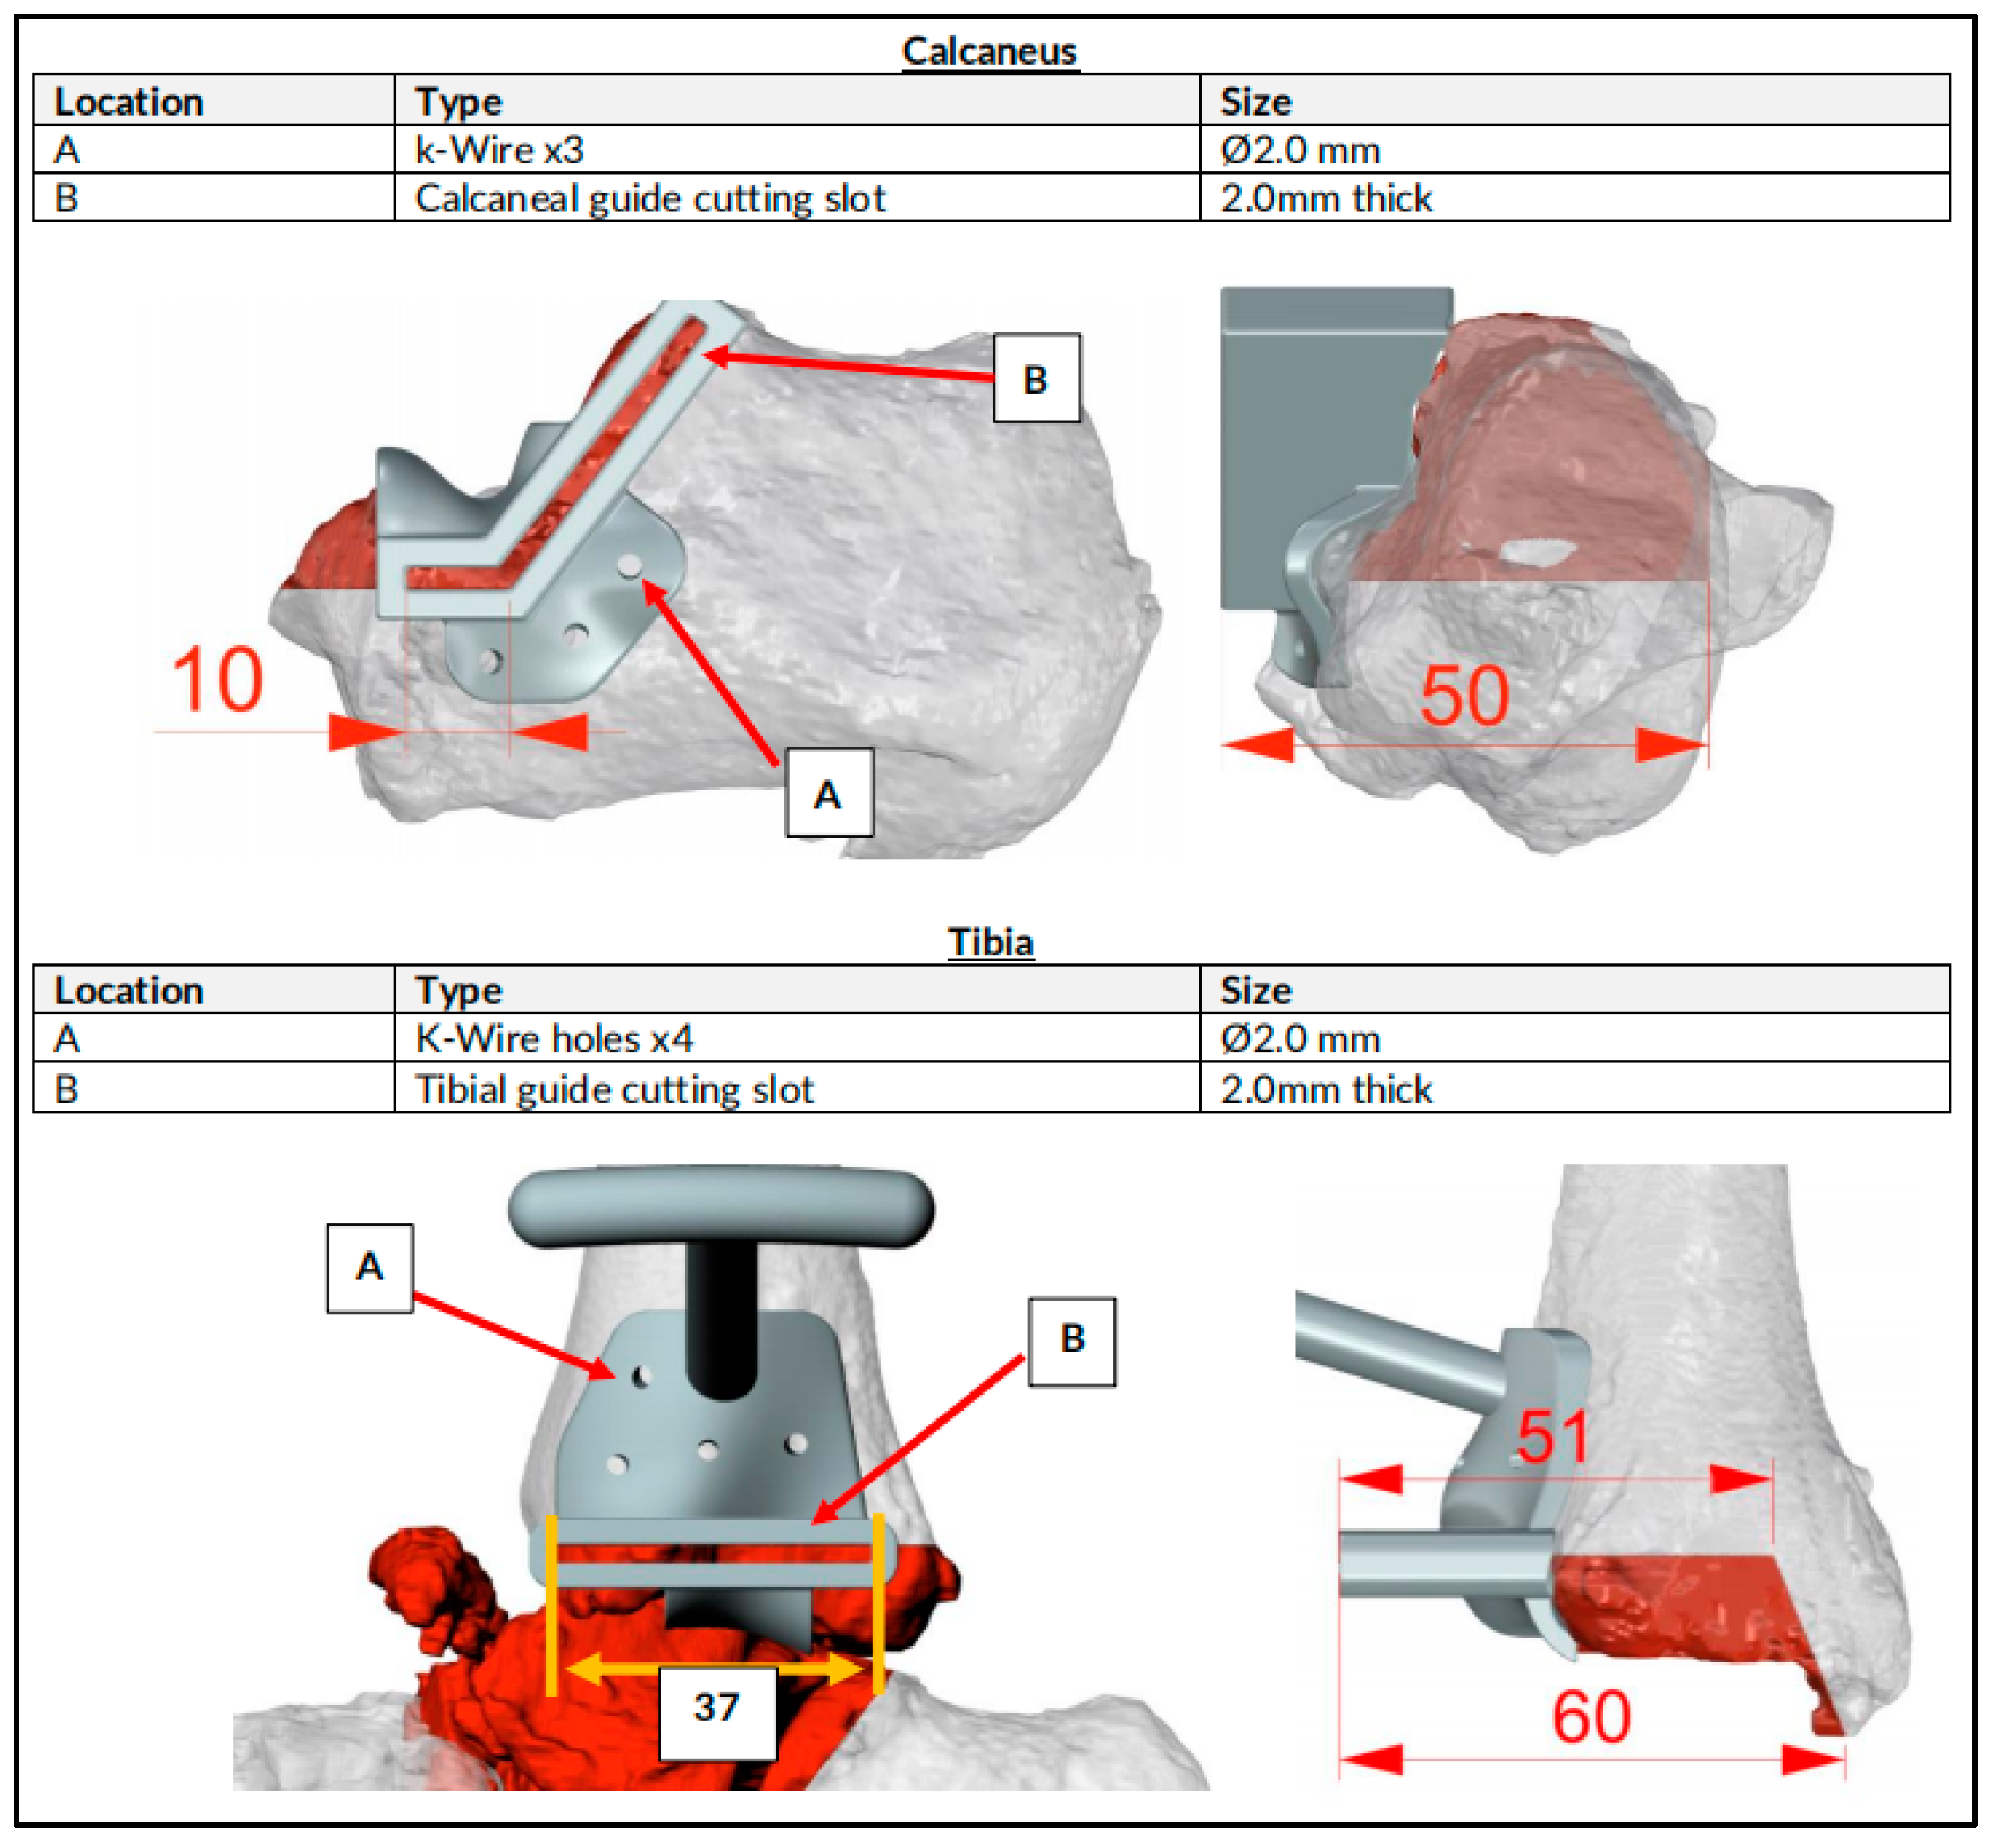

2.1. Preoperative Planning

2.2. Surgical Technique